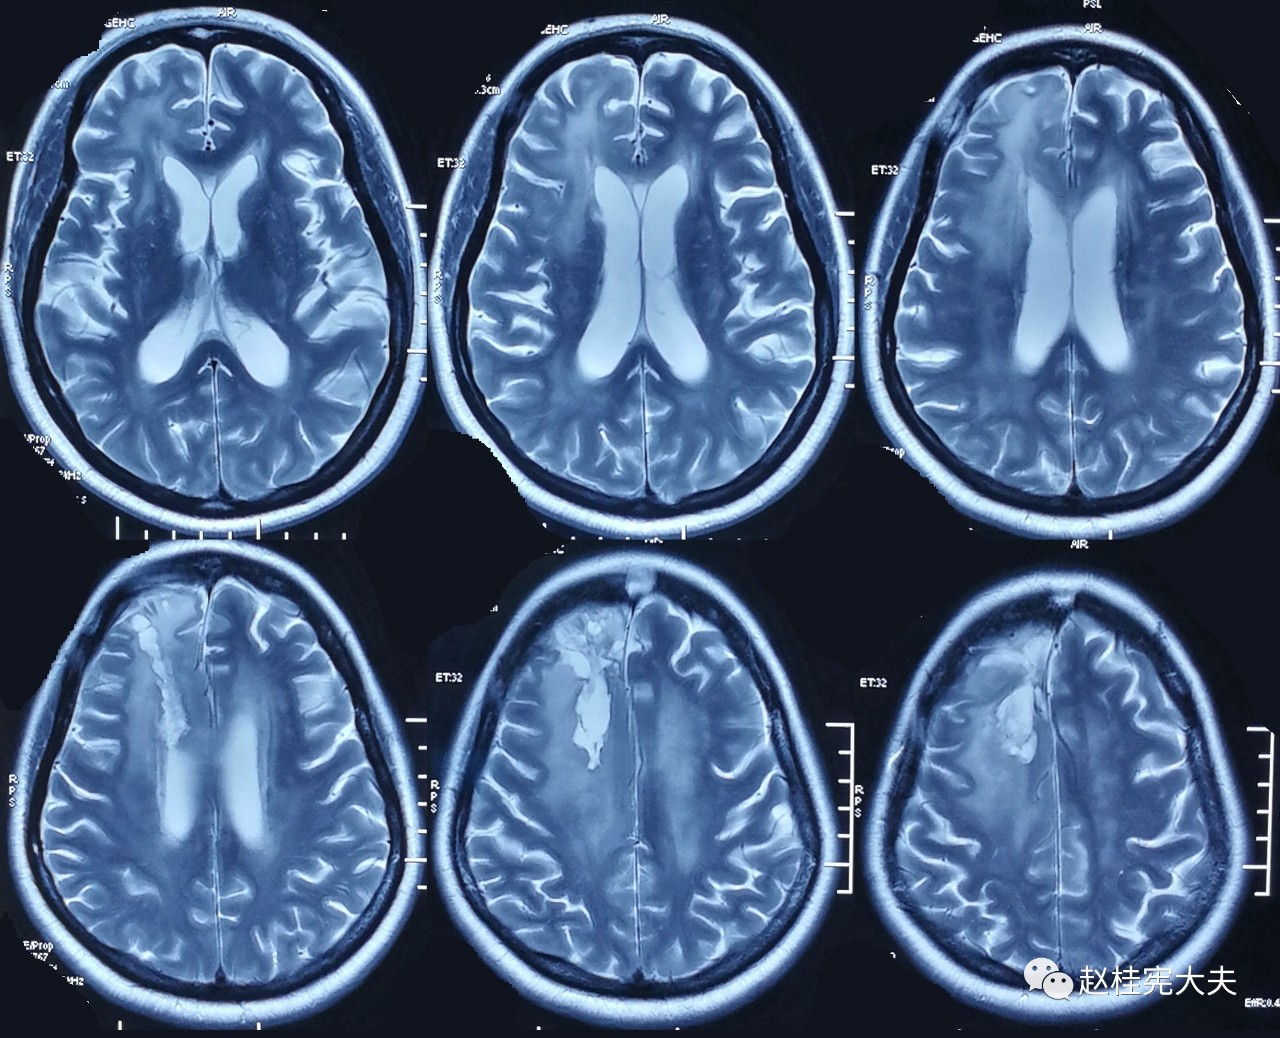

为了更直观,我们先看看其中1例患者的脑白质病变影像学的改变吧:

2017.10

可以看到,随着时间的延长,脑白质的T2异常信号范围不断扩大,并且出现了脑室扩大,脑萎缩。